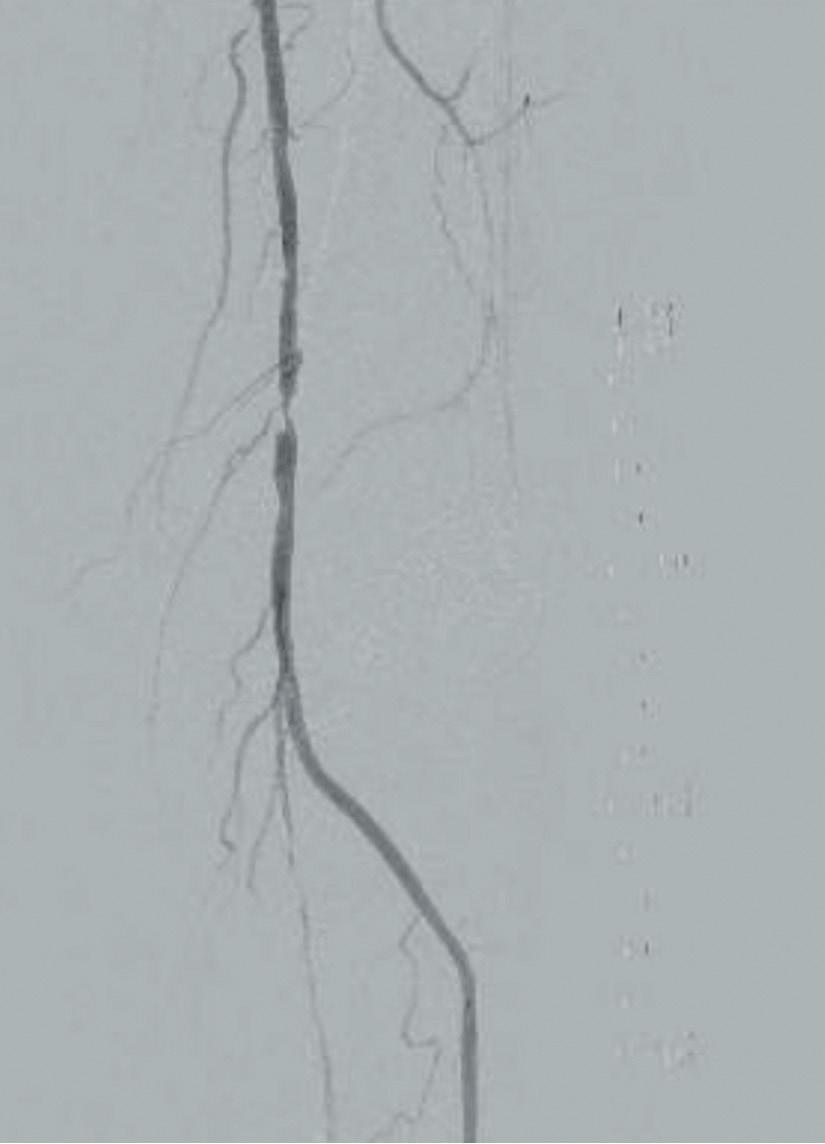

Significant life and limb gains for claudicants who stop smoking before lowerextremity bypass

LONG-TERM OVERALL survival (OS) and amputation-free survival (AFS) are outcomes that rebound in claudicants who quit smoking prior to elective surgery—and they mirror those of never smokers. But patients who do not kick the habit have significantly worse outcomes, lighting up the question: should stubbing out for good be “a requirement” before intervention?

That was the message from Rohini J Patel (University of California San Diego, San Diego, USA), who presented data at this year’s Society for Vascular Surgery (SVS) Vascular Annual Meeting (VAM 2023; 14–17 June, National Harbor, USA) on long-term outcomes in the smoking claudicant after elective lower extremity bypass. The findings were published simultaneously in the Journal of Vascular Surgery (JVS).

Patel noted that patients and vascular specialists must grasp that structured smoking cessation should be a more

prominent part of vascular office visits before and after lower extremity bypass and can “even be considered a requirement prior to elective procedures in claudicants”, a group that represents a unique non-emergent vascular patient population that can require lower extremity bypass.

Smoking is known to increase complications, including poor wound healing and coagulation abnormalities, and have cardiac and pulmonary ramifications, said Patel. “Across specialties, elective surgical procedures are commonly denied to active smokers. Given the base population of active smokers with vascular disease, smoking cessation is encouraged but is not required the way it is in general surgery,” she explained.

The research team queried the Vascular Quality Initiative Vascular

Implant Surveillance and Interventional Outcomes Network (VISION) database

over a 16-year period to tackle the question of how actively smoking claudicants fare after elective lower extremity bypass. They then carried out two separate propensity score matches on patient records that included 609 (10%) never smokers, 3,388 (55.3%) former smokers, and 2,123 (34.7%) current smokers who underwent bypass for claudication. One analysis examined the outcomes of former smokers and compared these to outcomes achieved in patients who had never smoked. The second analysis contrasted outcomes between current smokers and former smokers. The primary outcome measures included five-year OS, limb salvage (LS), freedom from target lesion reintervention (FTR) and AFS.

Health gains do not shift unless claudicants quit smoking

There were no differences recorded with respect to any of these measures between 497 well-matched pairs of former smokers and those who had never smoked. The second analysis, which focused on ascertaining outcome differences between 1,451 wellmatched pairs of current and former smokers, found that there was no

difference in LS or FTR, but revealed “a significant increase in OS and AFS” in former smokers compared with current smokers, suggesting that giving up smoking reaps rewards in terms of both limb and life preservation.

“Our study found that former smokers have better OS and AFS when compared to current smokers, while former smokers mimic never smokers at five-year outcomes for OS, LS, FTR and AFS,” Patel averred.

Patel states: “This study emphasises that we as providers must spend more time and effort working with patients to quit smoking prior to elective lower extremity bypass in claudicants.”

Limitations of the study include that the database contained no information on the duration or intensity of smoking among the study population.

According to senior author Mahmoud Malas (University of California San Diego): “Previous studies have shown that smoking cessation might not necessarily affect an immediate outcome in patients. We have found through this VISION database that even quitting one month prior to surgical intervention can change longterm outcomes.

“Former smokers do better than current smokers and former smokers mimic the results of patients who have never smoked. As vascular surgeons, we need to play a more active role in these discussions with patients in the clinic.”